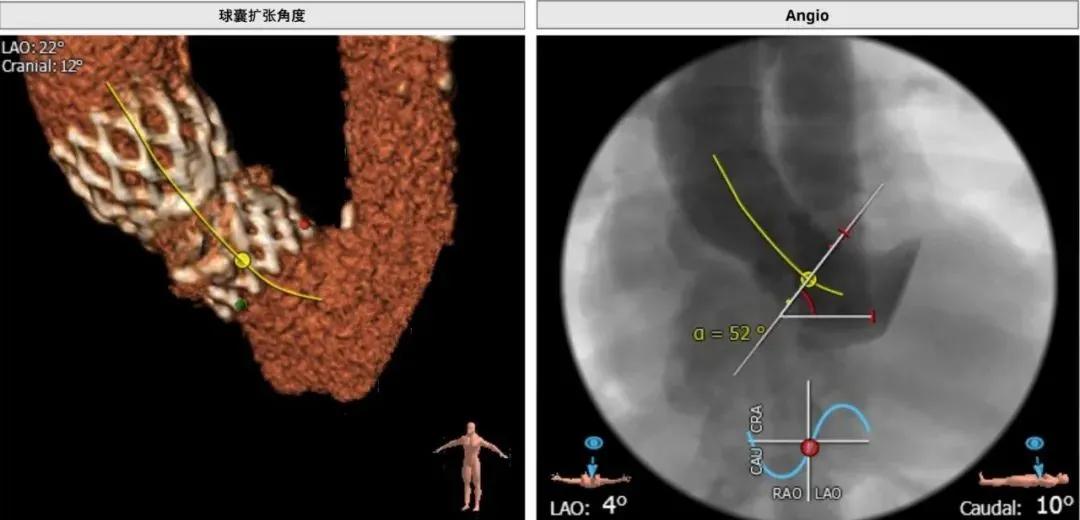

术前CT提示,患者主动脉瓣瓣环平均直径21.3 mm,瓣口面积351.3 mm 2 ;主动脉窦与窦管交界偏小,且冠脉开口偏低,冠脉阻塞风险偏高。该患者既往植入的是一枚美敦力23号Corevalve瓣膜,综合术前评估结果,决定为该患者植入20 mm Sapien 3球扩瓣一枚,并先行球囊扩张处理(BAV),判断瓣膜植入后是否会影响患者的冠脉血流状况。

以右侧股动脉为主入路建立双侧入路,Edwards Sapien 3球囊扩张式瓣膜输送系统顺利过弓、跨瓣;随后,行BAV观察患者血流动力学变化情况;